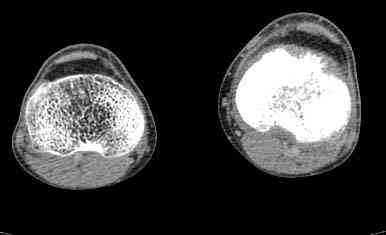

важаемые коллеги! Поступил больной 22 лет. Болен с января 2006 - появились боли в области верхнейтрети голени. При первичном осмотре в поликлинике был заподозрен первично-хронический остеомиелит - осмотрен гнойным хирургом - произведена биосия . Заключение - хондросаркома. Осмотрен онкологом - с учетом характера опухоли - химиотерапия, лучевое лечение не показано. Предложена либо ампутация, либо решение вопроса о возможности выполнения органосохраняющей операции. При обращении к нам произведена сцинтиграфия скелета - зоны гиперфиксации РФП: верхняя треть голени- 960%, нижняя треть бедра - 380%, Дистальный метафиз голени и затылочная область - 140%. В легких - метастазов нет. Произведена КТ (картинки в приложении). Учитывая абсолютную нестыковку рентгенологических и морфологических данных повторно биопсия. Выявлено, что первичная биопсия выполнялась из поверхностной параоссальной зоны - там локализованы хрящеподобные массы, далее очень плотная кость без хрящевых участков - биоптат взят фрезой с большим трудом. Морфологического заключения пока нет. Хотелось бы узнать Ваши варианты диагноза и соответственно тактику.

Не специалист по онко ортопедии, но по локализации (бедро, большеберцовая и плечевая кость), возрасть, в данный момент отсутствия метастаза и формация новой кости с мягкотканним вовлеченим, процесс больше напоминает остеосаркому большеберцовой кости.